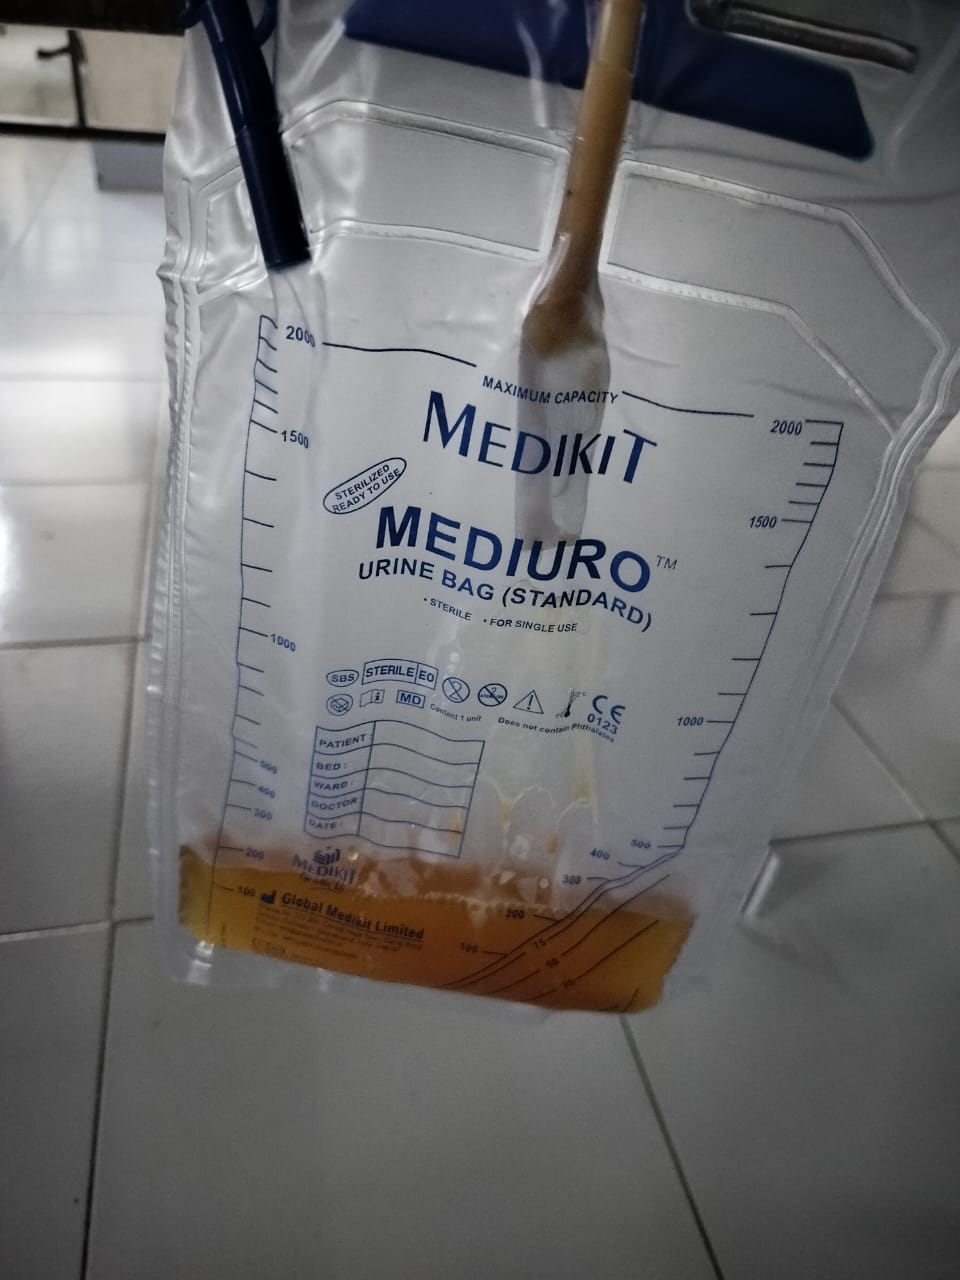

[24/06, 12:53] Rakesh Biswas: His urinary bladder bleeds appear to have stopped and foleys is functioning well although urology review today would be useful

[8/6, 9:22 AM] PaJR PHR Moderator: Urine culture sent?

[8/6, 9:23 AM] PaJR PHR Moderator: Remove old foleys. Send fresh urine culture from the first few drops of urine that come out while putting in the new foleys catheter

[8/6, 9:32 AM] +pajr_member: Yes sir

[8/6, 9:44 AM] PaJR PHR Moderator: After removing old foleys? How old was it?

[8/6, 9:46 AM] pajr member: Yesterday s sir

[8/6, 9:48 AM] PaJR PHR Moderator: 👆This catheter was inserted when?

Was the urine culture collected after removing this and reinserting a fresh one?

Can you share an image of the freshly inserted one?

[8/6, 9:57 AM]pajr_member: Yesterday after inserting foleys turbid urine came which was sent for cue and urine c/s and after sometime urine became normal sir

[8/6, 10:17 AM] PaJR PHR Moderator: That's strange!

[8/6, 10:20 AM] pajr member: 60M needs an USG? perhaps abscess near bladder neck?

[8/6, 10:22 AM] PaJR PHR Moderator: Yes given his past history of intermittent Hematuria also mentioned in his EMR horcrux here: https://www.facebook.com/share/p/vjAFKrL8AYQ29iTt/?mibextid=oFDknk

@pajr_doctot please get a urology opinion again today and remind them of all the ordeals they had during the last admission 3 months back to stop his hematochezia